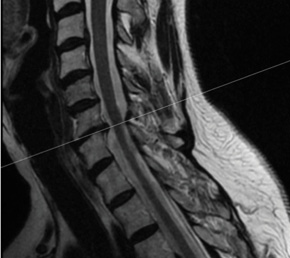

This patient is a 58 year-old female radiology technician with chronic, intractable neck pain, right > left arm radicular pain, and progressive weakness. At one point her symptoms worsened so acutely, she presented to the emergency department for acute triage with cervical CT angiogram, which showed advanced spondylosis at the C6/7 level.

The combination of the chronic problem with acute worsening of symptoms required decompression and stabilization at C6/7. Typically, at this patient age, with this advanced level of spondylosis at the C6/7 level, I would proceed with an instrumented fusion. However, this patient was very active and wanted to optimize her quality of life as possible with this surgery.

Patient is a healthy, active 58 year-old female, though with advanced degenerative spondylosis at a low cervical level. The patient had favorable anatomy with a long neck and low shoulders to facilitate intraoperative visualization. Fusion was appropriate in this case, but intraoperatively, though we were prepared for this possiblity, the disk space was well-preserved and mobilized without major modification of the endplates. The postoperative flexion and extension radiographs showed movement at the spinous processes of C6/7 and good function of the prodisc C Vivo prosthesis. The adjacent C5/6 level also shows degenerative spondylosis. By optimizing the mobility of the C6/7 level I anticipate the patient will have an improved trajectory for her cervical spine function throughout her life.